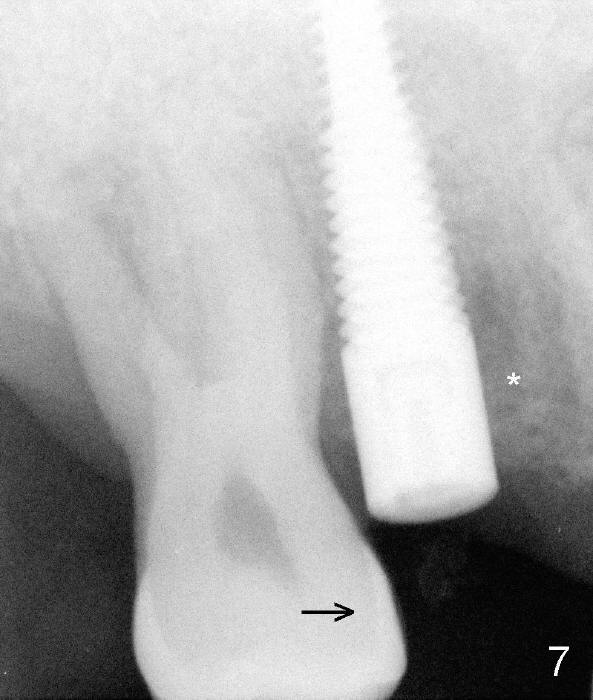

A 51-year-old man requests taking care of hemorrhage and odor associated with the tooth #3 (Fig.1). Due to religious and financial issues, the neighboring teeth will be treated later (supraeruption of #2 (arrow) and periapical radiolucency of #4 (*)). CBCT reveals that the septum of #3 is large enough to hold 4.5 mm implant (Fig.2). In fact osteotomy is created as planned in the septum using drills and taps (Fig.3 after removing 4.5x20 mm tap). Primary stability is obtained with a 4.5x20 mm implant (> 60 Ncm, Fig.4). The gap (*) is bone grafted; an abutment is placed (Fig.5 A); an immediate provisional is fabricated and cemented to cover the socket (Fig.6 P). When the socket heals in 3 weeks postop, the provisional and the abutment are removed for easy oral hygiene. Bone regenerates around the implant 3.5 months postop (Fig.7 *), but the 2nd molar has shifted mesially (arrow), presenting a restoration challenge.

Solution? An abutment is placed and a provisional crown with occlusal contact with the opposing is fabricated. A separator is placed between #2 and 3. Once a space forms, acrylic will be added the distal surface of the #3 temporary crown, which is then recemented. A new separator is used to create more space between these two teeth until #2 is distalized.

It appears that the upper molar shifting is quite common (6 7), probably due to less dense bone in the maxilla. It is the best to fabricate and keep an immediate provisional to hold the mesiodistal dimension and ask the patient to improve local oral hygiene during osteointegration. The implant crown is functioning 4 years 2 months post cementation while there is severe bone loss at #2 (Fig.8). An immediate implant could be placed at #2 (Fig.9), while a wide delayed implant will be placed at #31 (Fig.10).